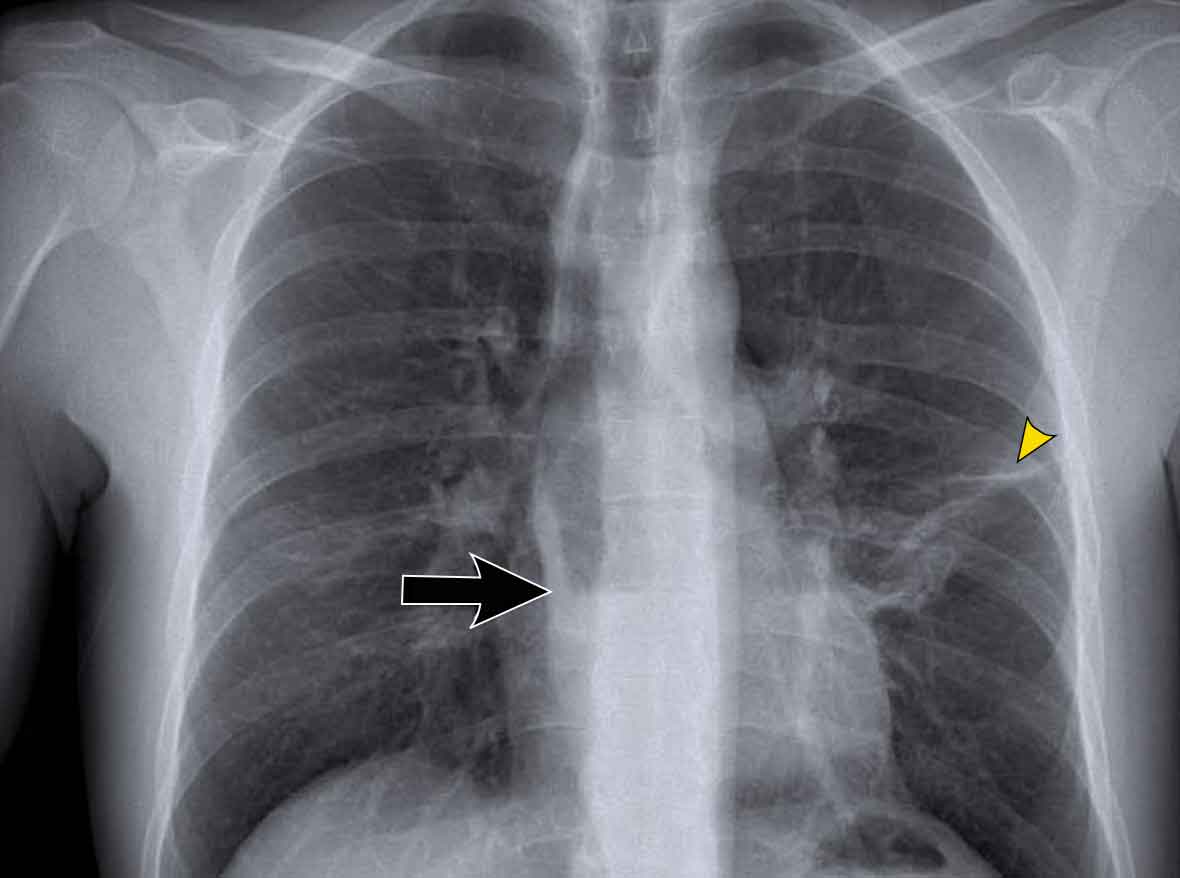

Hidden Areas (2): Right Lower Lobe Lesion

This example demonstrates a large mass in the right lower lobe that is challenging to identify on the PA view unless close attention is paid to the hidden areas.

- On initial inspection, the lesion is inconspicuous.

- However, with focused review of the subdiaphragmatic and retrocardiac regions, the abnormality becomes evident.

- Enlarge the image for better visualization.

Hidden Areas (3): Pneumonia Below the Diaphragm

In this case, a pneumonia was primarily located below the right diaphragmatic dome (yellow arrow), within the posterior basal segment of the right lower lobe.

- On the lateral view, there is an increase in opacity over the lower thoracic vertebrae, indicating lower lobe consolidation (arrow).

- Again, image magnification may be necessary for adequate assessment.